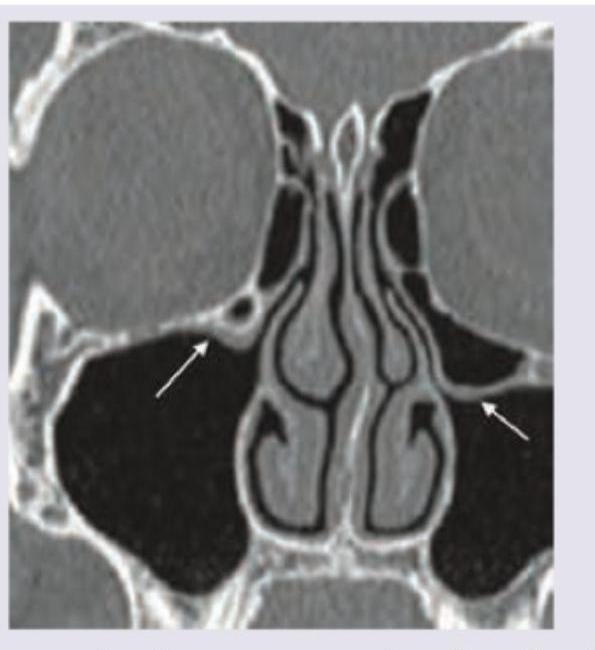

The CT scan of paranasal sinuses shows:

Explanation: ***Haller cells*** - The image shows **pneumatized ethmoid air cells** located inferior to the orbit and lateral to the maxillary sinus ostium (arrows), which are characteristic of Haller cells. - These ethmoid cells, also known as **infraorbital ethmoid cells**, can narrow the maxillary sinus ostium, potentially contributing to **recurrent sinusitis**. *Agger nasi cells* - **Agger nasi cells** are the most anterior ethmoid cells, located in the lacrimal bone, anterior and lateral to the frontal recess. - They are typically situated at the level of the frontal sinus ostium, not inferior to the orbit. *Onodi cells* - **Onodi cells** are sphenoethmoidal air cells that extend posteriorly and laterally over the sphenoid sinus, in close proximity to the optic nerve. - Their location is **posterior and superior** to the structures shown in the image, making them incorrectly identified here. *Frontoethmoid cells* - **Frontoethmoid cells** can be a broad category, but specifically refer to ethmoid cells that extend into the frontal sinus or drain into the frontal recess. - While they are ethmoid cells, the specific location shown in the image (inferior to the orbit and maxillary sinus ostium) is more precisely described as Haller cells.